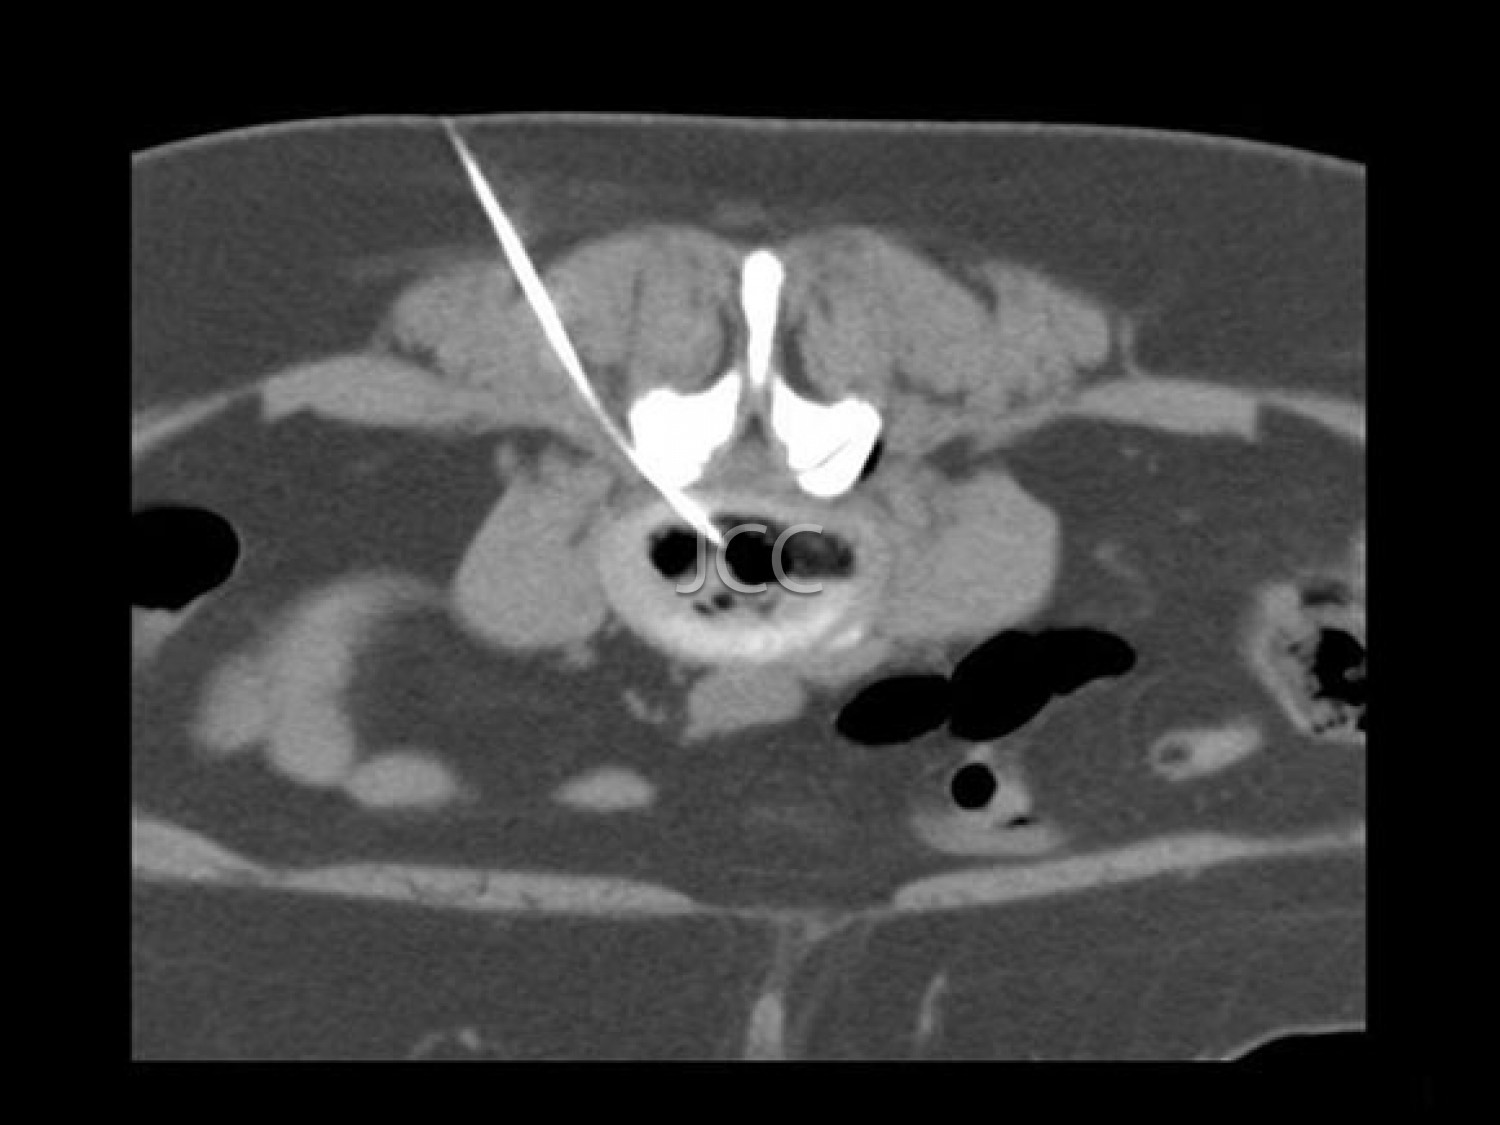

- Interventional Radiology